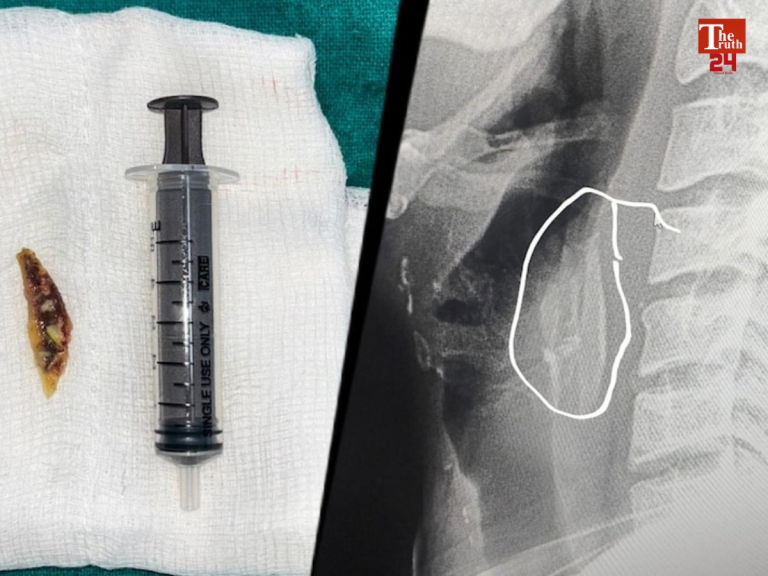

मध्य प्रदेश के शाजापुर जिले में चिकन खाते समय एक 24 साल के युवक के गले में...